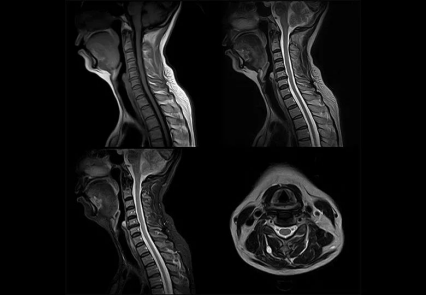

核磁共振MRI

原理簡介:MRI的工作原理是讓共振人體的氫離子產(chǎn)生共振來產(chǎn)生圖像。我們?nèi)梭w有很多H2O,也就是水!所以,有水的地方氫離子多,反之則少,也就是說有水的地方核磁共振做得清楚,沒水的地方就做得不清楚。因此人們也戲稱它是搖一搖再看的檢查。

應(yīng)用:擅長檢查軟組織

優(yōu)點:輻射很小,沒有骨性偽影,能多方面、多參數(shù)成像,有高度的軟組織分辨能力;

缺點:檢查時間長,費用相對高;

磁共振圖像舉例

骨骼和鈣化的地方水最少,所以如果你骨折了,說要拍個X線片是可以的,做個CT檢查也可以。但要是做核磁共振掃描,那我勸你還是別做了,因為核磁共振看不清楚。但是,骨骼邊上的那些肌肉,關(guān)節(jié)的軟組織、韌帶等本來CT檢査是看不清楚的,核磁共振掃描卻一覽無遺。肌肉拉傷了,核磁共振能分辨哪根肌腱受損,損傷到什么程度。

除了肌肉、韌帶含水較多以外,腦的含水量也很大,所以腦部做核磁掃描也非常清楚。